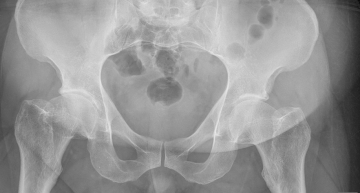

в последние три года периодически возникали боли в коленных суставах. амбулаторное и санаторное лечение приносило некоторое облегчение, на два три месяца. летом на даче стараюсь не перегружать суставы, занимаюсь посильным физическим трудом. но с августа 2013 появились сильные боли в левом тазобедренном и коленном суставах. по снимку, сделанному в поликлинике, врачи поставили диагноз: коксоартроз и возрастные изменения в коленном суставе. по предписанию врачей проколола мукосат 20 уколов и диклоберл 15 уколов, но улучшения не наступило. сейчас мучают дикие боли в левом тазоюедренном и коленном суставах, и при ходьбе очень болит берцовая кость. предложеные физиопроцедуры пройти не могу, так как практически не выхожу из дома. на некоторое время помогает нимесулид 100мг в таблетках. с каждым днем боли все сильнее, а лекарственное воздействие все меньше.